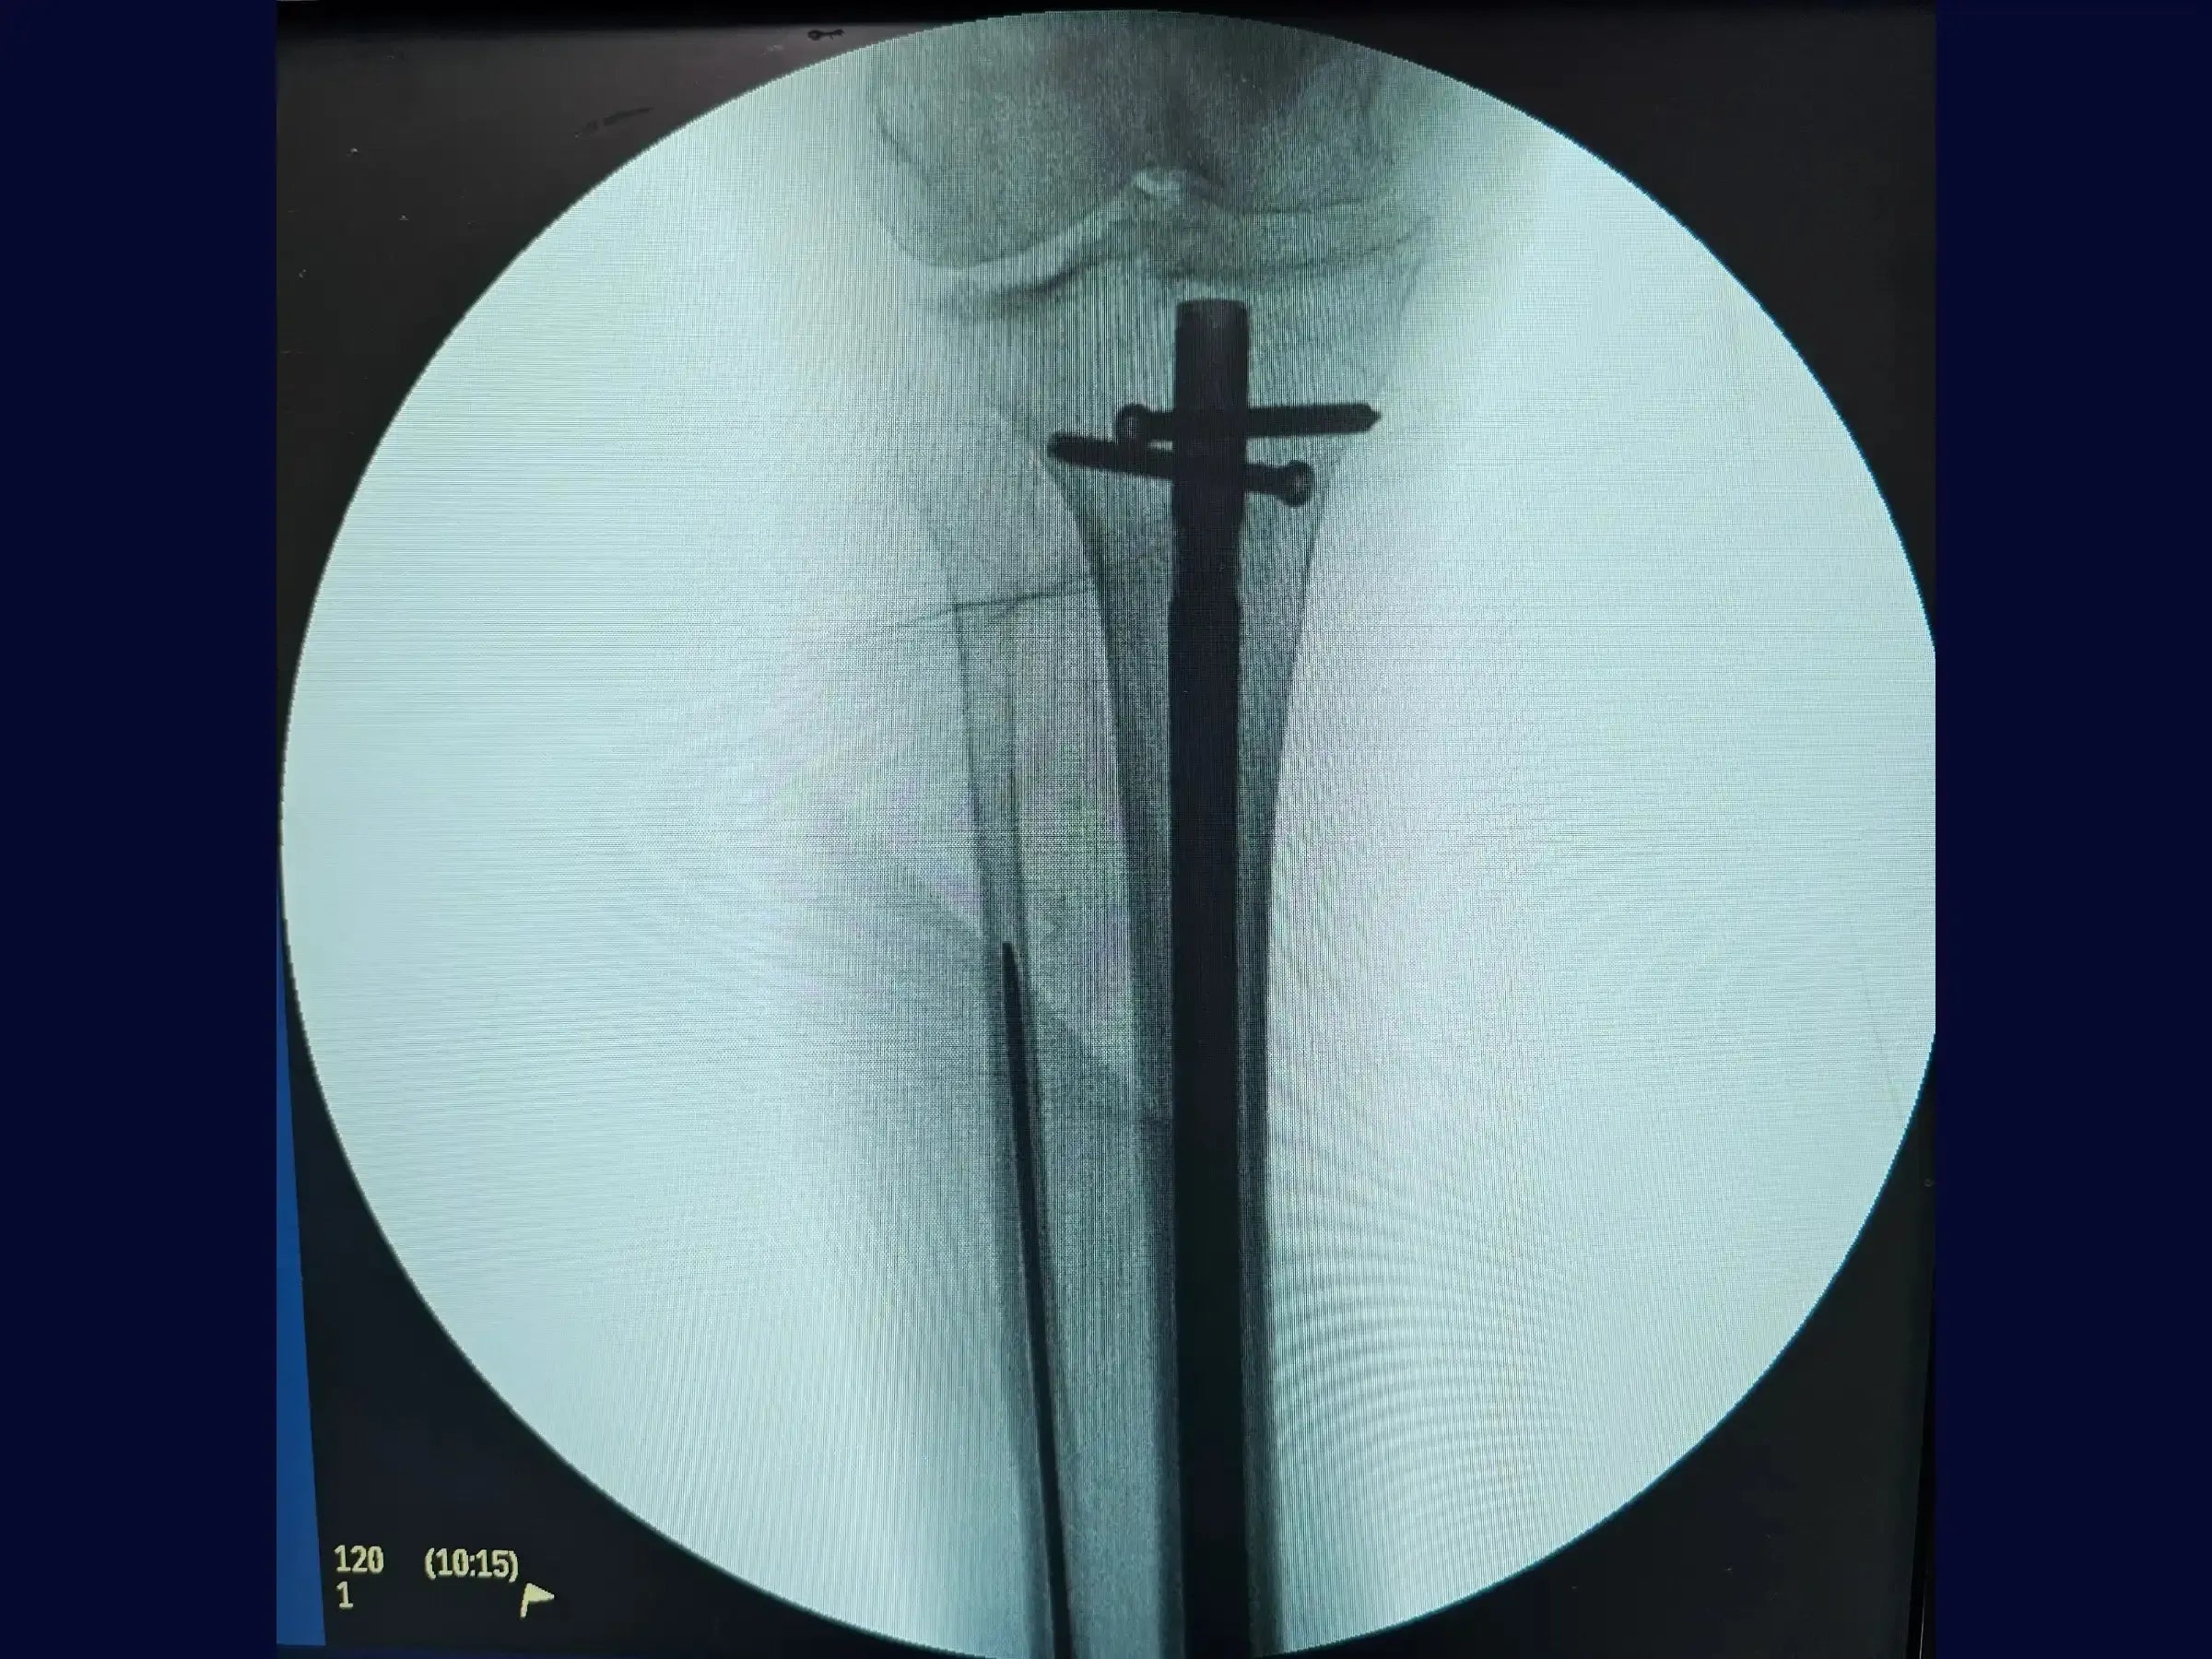

- Bloqueio Proximal e Distal: Execução do bloqueio proximal percutaneamente com o paciente mantendo a perna em posição estável, e técnica de "mão livre" para os parafusos de bloqueio distal, com marcação precisa da pele para evitar atrito com partes moles.